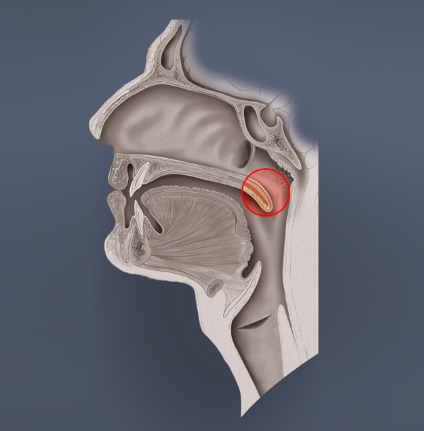

- Eustach’sche Röhre (Tuba auditiva, engl. Eustachian tube)

Die Tube ist eine 30 – 35 mm lange, mit Flimmerepithel ausgekleidete, Röhre, die das Mittelohr und den Nasenrachenraum verbindet. Ohne eine ausreichende Belüftungsfunktion ist der Druckausgleich unmöglich, da dies der einzige Zugang zum Mittelohr ist. Im Normalzustand ist die Tube geschlossen, öffnet sich jedoch beim Schlucken, Gähnen oder bestimmten Lauten und natürlich beim Druckausgleich.